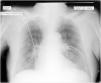

This is the case of an 86-year-old man admitted to our unit after emergency percutaneous coronary intervention due to anterior ST-segment elevation acute myocardial infarction with implantation of 2 drug-eluting stents into the LAD and first diagonal branch. Upon admission the situation of the patient remains hemodynamically and respiratory stable with 93% oxygen saturation on pulse oximetry without oxygen supply. A thoracic x-ray (Rx) is performed in the supine position that reveals the presence of 2 lines suggestive of bilateral pneumothorax (Fig. 1, arrows) that cannot be seen in the upper lobes (Fig. 1, arrowheads). To rule out the presence of bilateral pneumothorax, a bilateral thoracic ultrasound is performed that reveals the presence of pleural «sliding» on the imaging in M-mode or «seashore sign» (Fig. 2). In an Rx performed afterwards while in the semi-sitting position, only a small right baseline line can be seen (Fig. 3), and diagnosis of false bilateral skin fold pneumothorax is achieved.